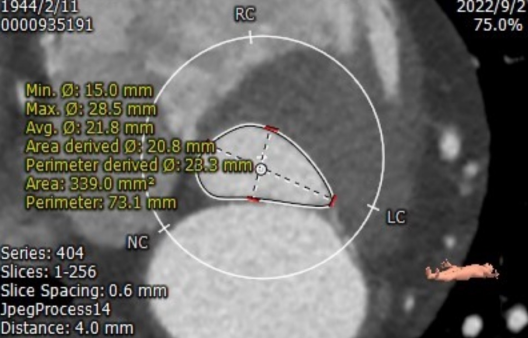

CT评估

1.瓣环及左室流出道

2.主动脉根部

3.外周血管入路

收缩期瓣环:70.3mm

收缩期流出道:72.2mm

舒张期瓣环:68.1mm

舒张期流出道:73.1mm

左冠高度10.8mm

右冠高度14.1mm

主动脉窦宽:32.8mm、31.3mm、32.4mm

窦管结合部:113.9mm

升主动脉:146.6mm